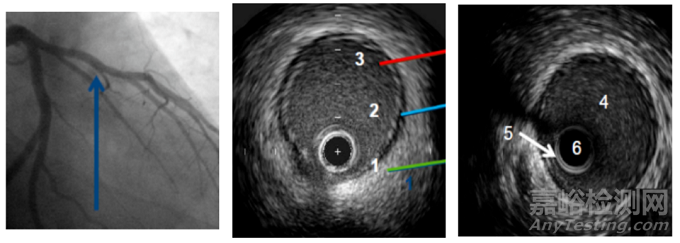

▲血管在超聲下的圖像

1: 外膜是由膠原蛋白組成,超聲反射信號強烈(顯示為白色)

2: 中膜是由平滑肌細胞組成,無超聲回波信號(顯示為灰色)

3: 內膜致密,介于中膜和血流之間,顯示為白色

4.管腔:血液

5.衰蕩區:“光暈”

6.盲區:導管